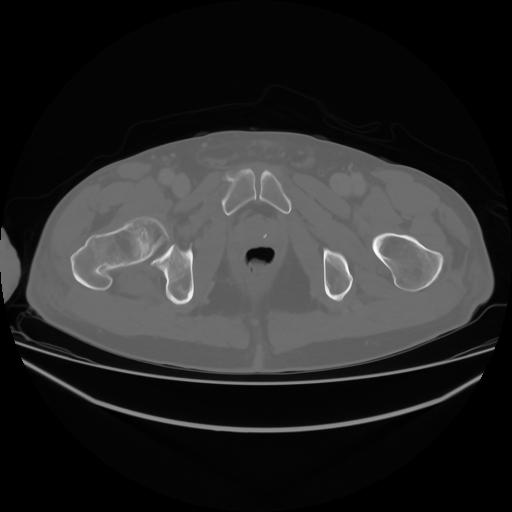

4 CUERPO,CE,Axial,3.0,CUERPO,,